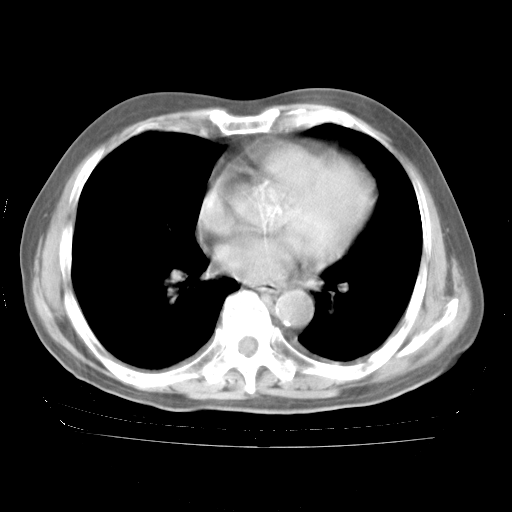

4月28日肺部CT——再次出现类似去年5月9日——透光度降低,“间质性”改变。